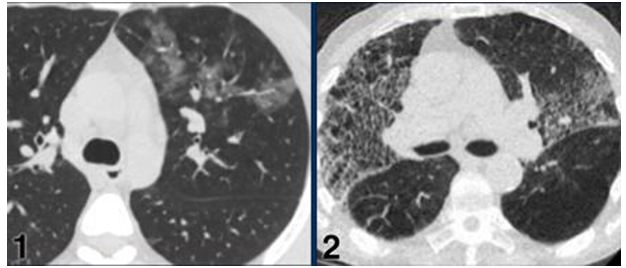

CO-RADS 4: Hình 7

Hình 7:

Trường hợp 1: Tổn thương GGO nhiều ổ bên trái thùy trên, PCR (+) với COVID 19

Trường hợp 2: Tổn thương GGO kèm theo thấy “Spider web sign” cả 2 bên